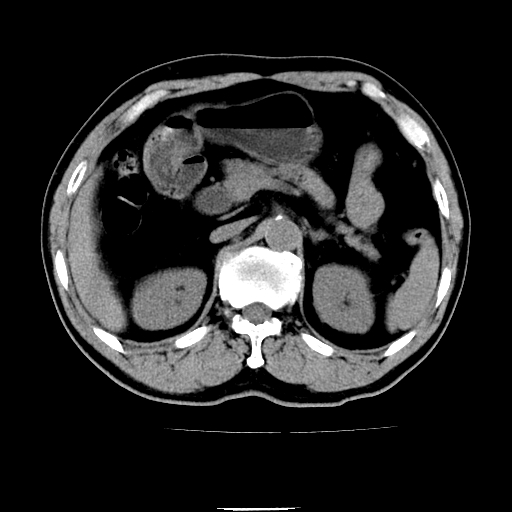

以下是引用chenqiong在2010-3-25 20:56:00的发言:[br]1、胆囊炎,胆囊息肉[br]2、肝内胆管及胆总管扩张,胆总管下端结石[br]3、十二指肠乳头旁憩室

以下是引用zxl51642在2010-3-26 10:47:00的发言:[br]胆囊炎,胆囊息肉,胆总管扩张,但未看到明显肿块,肝内胆管扩张不像恶性,炎性狭窄或阴性结石可能吧,建议mrcp,右肾小囊肿